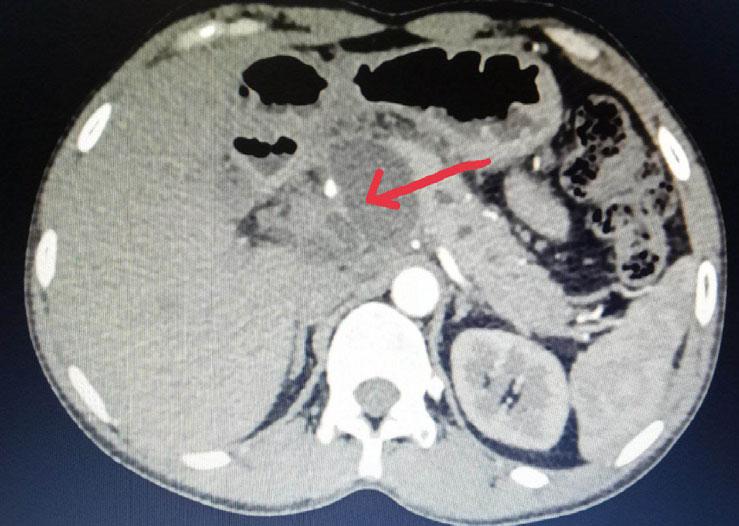

Materials and Methods : This prospective hospital-based study was conducted in the Department of General Surgery, Assam Medical College and Hospital, from January to August 2022. Twenty-five patients diagnosed clinically and radiologically with pancreatic pseudocyst were enrolled. Data on demographics, clinical presentation, etiology, imaging findings, management, and outcomes were collected and analyzed using SPSS v20. Patients were followed up for four months.

Results : Most patients were males (88%) with a mean age of 44.8 years. Alcohol was the predominant etiological factor (72%), and pain abdomen was the universal symptom (100%). Imaging with ultrasonography and CECT abdomen aided diagnosis. Internal drainage was the most common management (40%), followed by external drainage (32%) and conservative treatment (28%). Infection (24%) was the main complication. Recurrence was highest after conservative management.